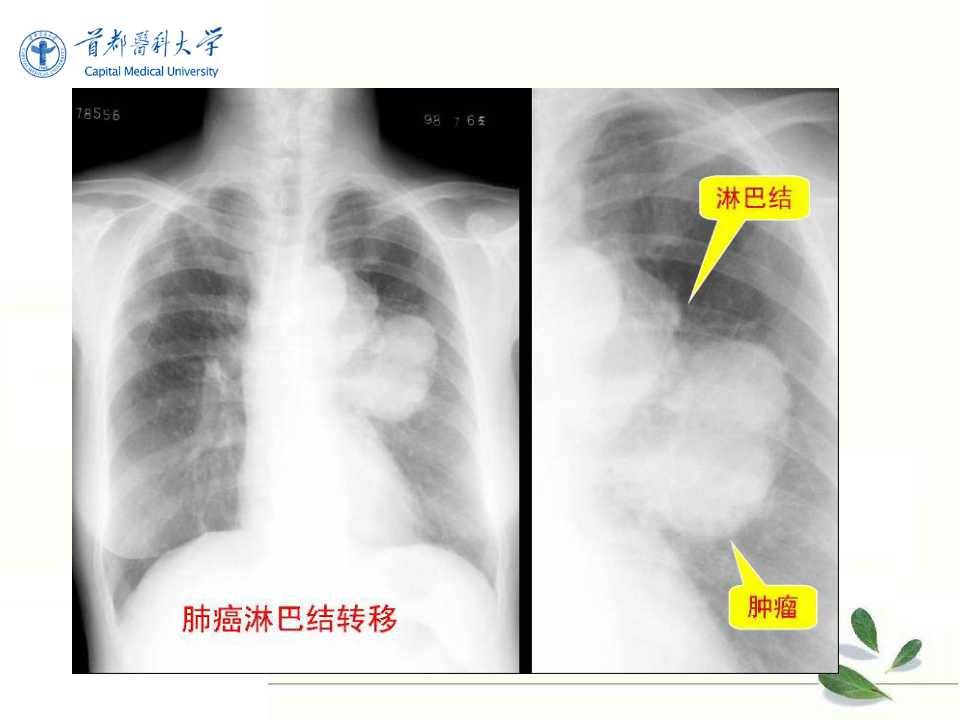

肺癌的影像学检查